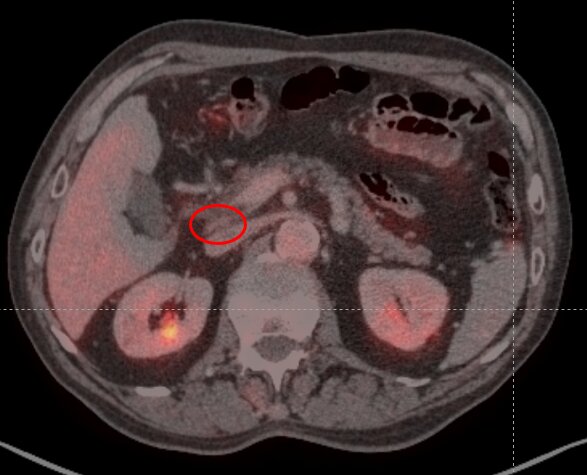

Полный регресс (ПЭТ/КТ от 28.10.2024, 18.02.2025; 08.10.2025).

ПЭТ/КТ от 18.10.2025 полный регресс опухоли

В послеоперационном периоде пациент продолжает принимать антиHER2-терапию (Трастузумаб эмтазин) для профилактики рецидива/прогрессирования заболевания. По данным ПЭТ/КТ (18.10.2025) сохраняется полный регресс болезни. Признаков кардиотоксичности на фоне терапии нет. Мужчина чувствует себя хорошо. Полон сил и энергии.